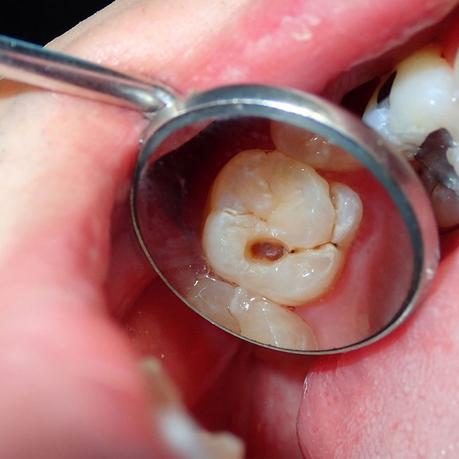

These microbes can be good or bad, and the bad ones can cause tooth decay. Many bacteria cause tooth decay: Streptococcus mutans, Streptococcus sobrinus, and Lactobacillus. This is not exaggerated: as soon as we eat something, our harmful, tiny microbes start to initiate a fierce battle in our mouths. The bacteria use every bit of leftover foods and drinks that contain sugar or starch as ingredients to produce acids that can eat away the tooth’s most rigid surface, the enamel. The wound in the tooth that we’ve noticed as the dental cavity and the surrounding devastating, sticky, transparent film of microbes as dental plaque. Battling the destruction the microbes have brought is the minerals in our saliva, consisting mainly of Calcium and Phosphate. After each acid attack, the saliva remineralizes the damaged enamel with Flouride from the toothpaste, water, and other sources. This battle of scraping minerals away and cementing them back to enamel is always happening at any time for as long as the person is alive. However, a constant acid attack may overburden the ability of saliva to heal the tooth. This means that the frequent eating and drinking of sugar and starch that we all love arms the bacteria to defeat the good guy, saliva. The enamel’s recovery rate will be outrun by the repeated cycles of acid damage, causing it to lose minerals. An early sign of decay may show in the form of a white spot where the mineral is lacking. If action is taken at this point, by supplying enough minerals and Fluoride, the enamel can still repair itself, and the decay can be stopped or even reversed. But if we keep consuming sugar and starch mindlessly, more minerals will be lost, and the decay process will continue beyond repair. The enamel will be weakened and eventually destroyed, forming a dental cavity. To save the damaged tooth, we require the help of a dentist to fill the hole with materials such as composite resin. Tooth decay can be avoided by eating or drinking less sugar and starches. Frequent use of fluoride-containing mouthwashes, gels, toothpaste, and tablets will also fortify the enamel.

Why do I have a cavity? Where does it come from? Well, consider this, your tooth is made of three main parts.

We have the outer layer, the enamel. That’s like the tough, hard candy coating shell. And then below that, you have dentin. That makes up most of your tooth, but it’s softer than the enamel. It’s kind of like an elephant’s tusk– ivory. And then inside of that, you have the blood supply and the nerve– protected, surrounded by the dentin, surrounded by the enamel. But then, outside of that, you have things

called bacteria living in your mouth. They do all sorts of beneficial things. But certain kinds of bacteria produce acid that can eat through the enamel. Once that happens, my friend, you have a cavity. And if that acid keeps going and keeps eating through the dentin, which it can make it through way faster than it can the enamel, well, eventually, it’s going to make it to the nerve. And then you have a huge problem. It’s called a nerve that’s on fire with pain because you have a cavity going from the outside to the nerve. And things like water and air and turkey can make it down to this nerve, and you’ve got a lot of pain and need a root canal. So brush your teeth. It’s all you have to do. If you brush your teeth, you are combating the plaque buildup, which is just a bunch of this acid put out as, well, bacterial poop as it’s eating the stuff on your teeth. It all comes back to brushing your teeth.